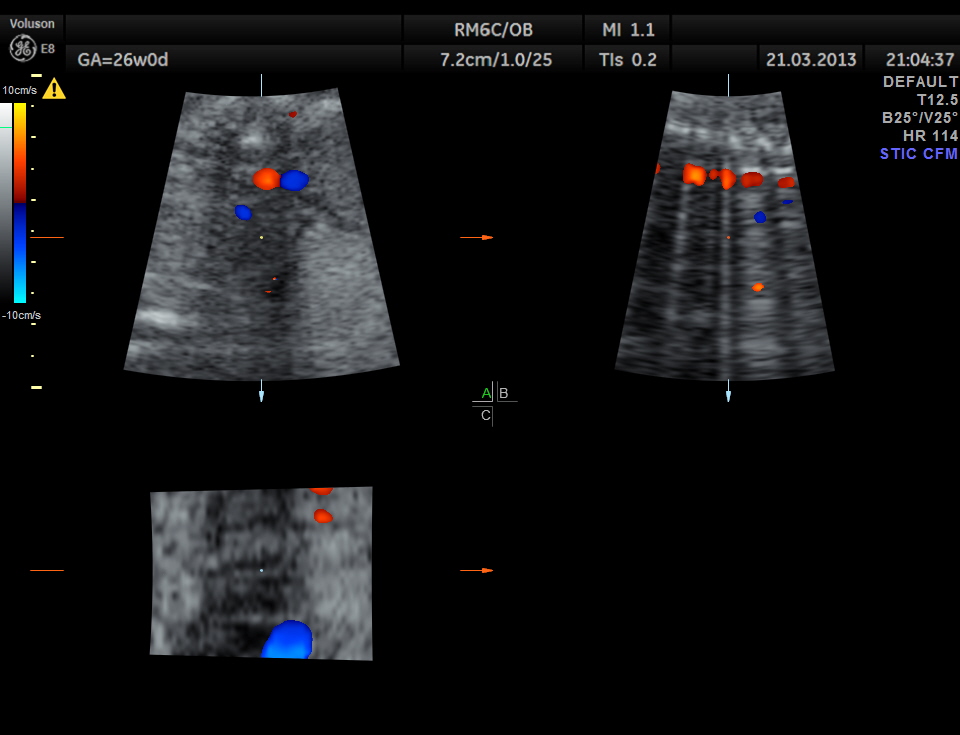

STIC image shows ATRIO VENTRICULAR SEPTAL DEFECT ( ENDOCARDIAL CUSHION DEFECT )